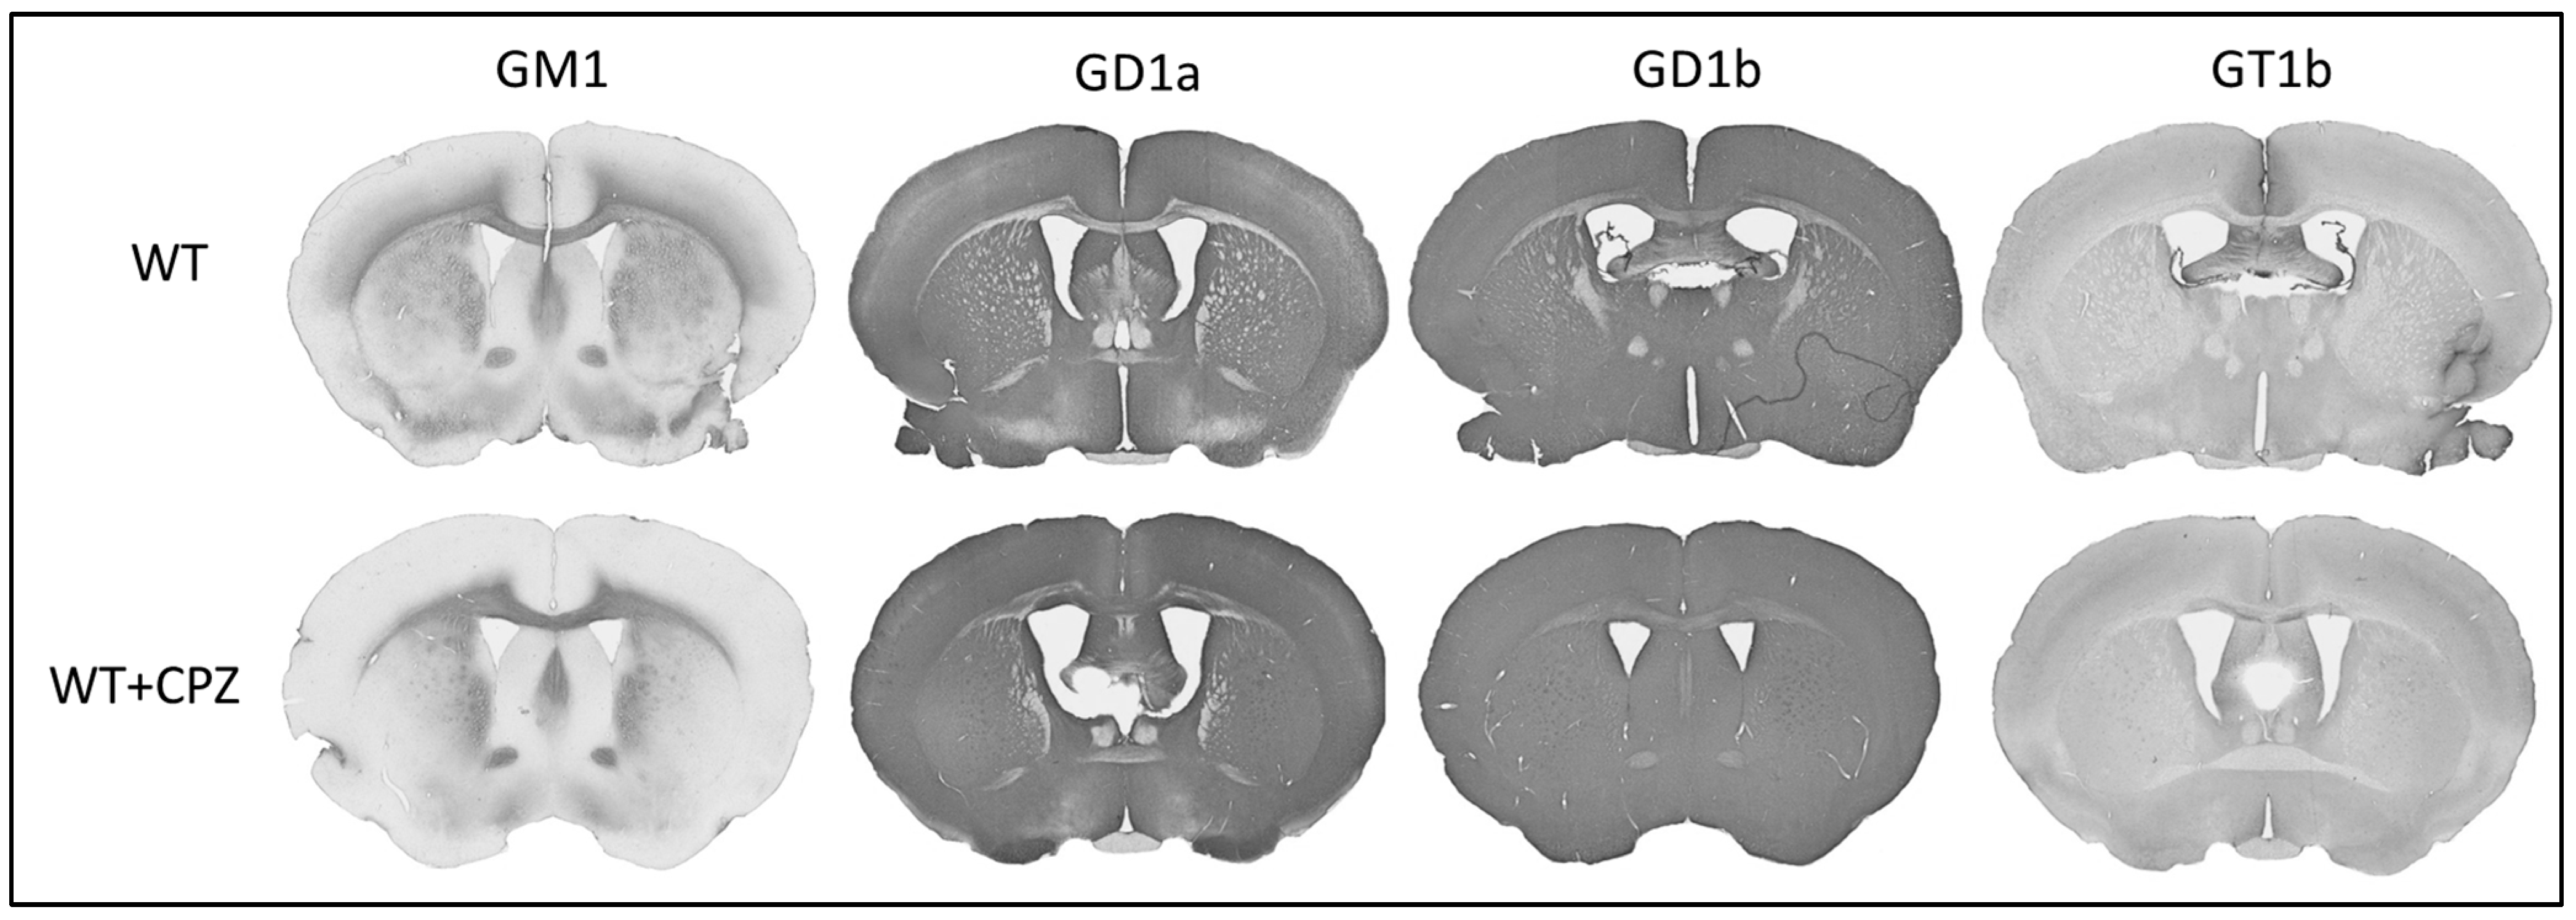

In addition to assessing the extent of demyelination by cuprizone treatment, we also investigated whether this treatment altered the distribution of gangliosides. Figure 6 shows the immunohistochemistry of coronal sections of forebrain from WT mice and WT + CPZ mice labeled with antibodies against the four most abundant brain gangliosides (GM1, GD1a, GD1b and GT1b), which are not present in KO mice. The overall distribution for all four antibodies is virtually identical in the forebrain (Figure 6). However, when we analyzed the corpus callosum, the quantification results showed a significant increase in three (GM1, GD1a and GT1b) of the four complex gangliosides (p < 0.01). Only ganglioside GD1b was not increased in WT + CPZ animals compared with WT animals (Figure 7).

Figure 6. Immunohistochemical staining of the four major brain gangliosides (GM1, GD1a, GD1b and GT1b) in the brains of wild-type (WT) and cuprizone-treated wild-type (WT + CPZ) mice on coronal sections of the forebrain.